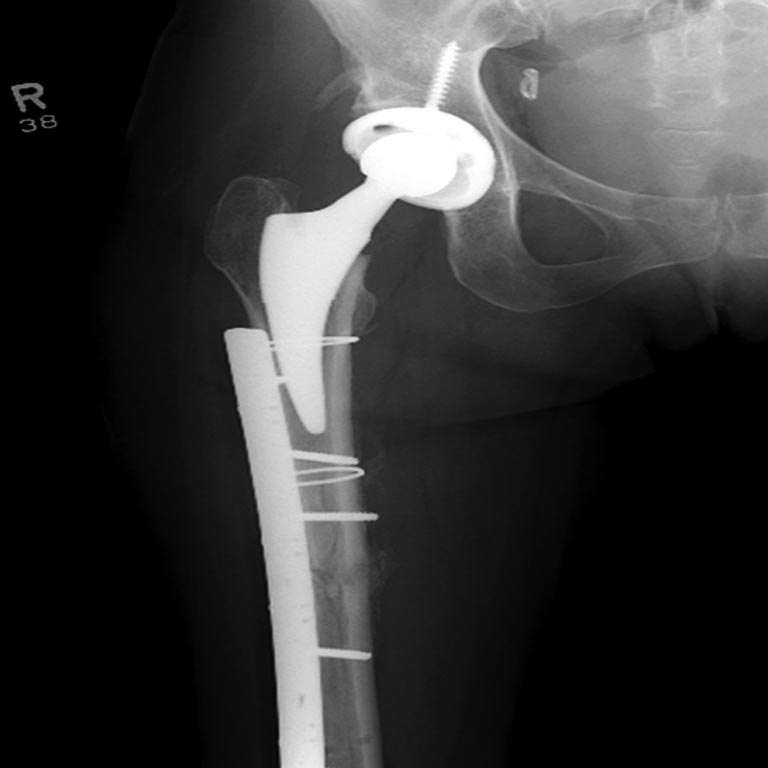

Из вариантов фиксации для проксимального и диафиза бедра выбрали пластину, а по поводу артропластики остается вопрос между тотальным или геми.

На 25 день с момента травмы операция на Jackson table с боковым обширным доступом. Удаление стержней с местной обработкой. В тазобедренном суставе удаление головки, на дне вертлужной впадины полная отслойка хряща. Вертлужный компонент с одним винтом и короткая ножка - Fitmore press fit stem. На второй день однократно доза радиации для профилактики гетеретопической оссификации. Послеоперационный период без температуры. Выписана. Нагрузку разрешили на левой стороне, а полная в 3 мес. Здесь снимки при амбулаторном наблюдении: послеоперационно, 2 мес, 3 мес и 6 мес. Нагрузка полная, отсутствует хромота, и нет жалоб.